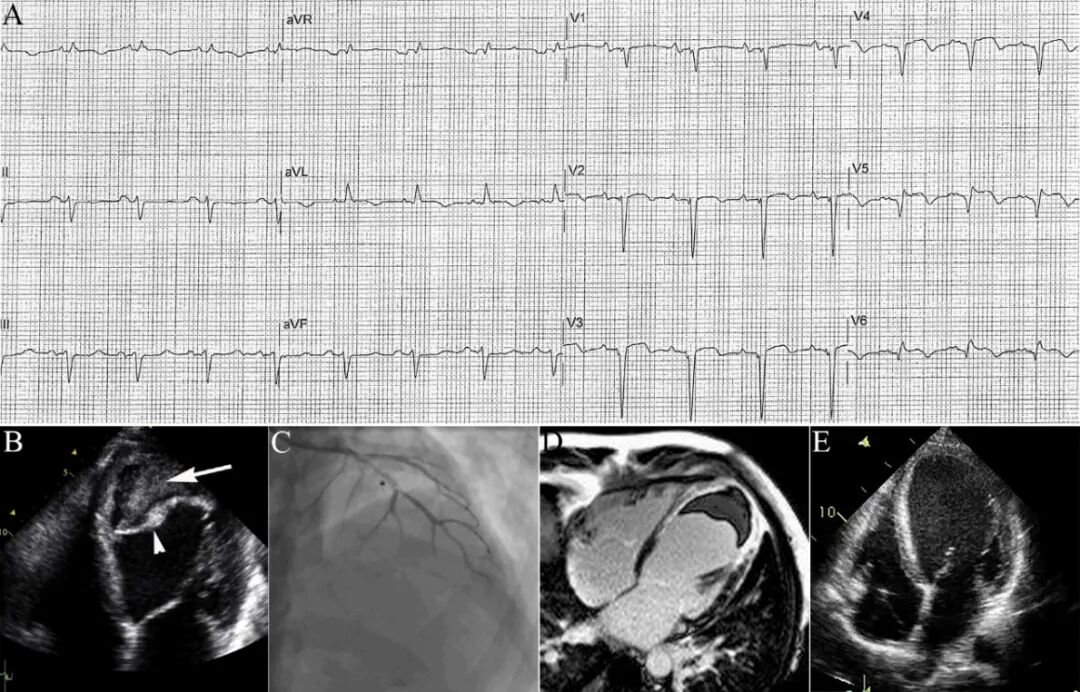

图2 AMI并发自发性心肌壁内血肿[2]。

42岁男性,劳力性呼吸困难2周,无胸痛病史和心血管危险因素。心电图示胸前导联广泛Q波形成(A)。心超示左室心尖部、前壁活动消失,LVEF<20%;最大发现是左室心尖部巨大混合性团块,声学造影和多普勒检查均未发现团块与心腔相通,也无心包积液,考虑心梗后心肌内血肿(B)。冠脉造影显示前降支中段次全闭塞(C)。增强CMR显示心肌梗死合并左室壁内血肿形成伴心尖部少量附壁血栓(D)。多学科会诊后决定保守治疗。住院期间反复出现持续性单形性室速,电复律后植入ICD。出院后6个月复查心超显示心肌壁内血肿和附壁血栓消失(E)。